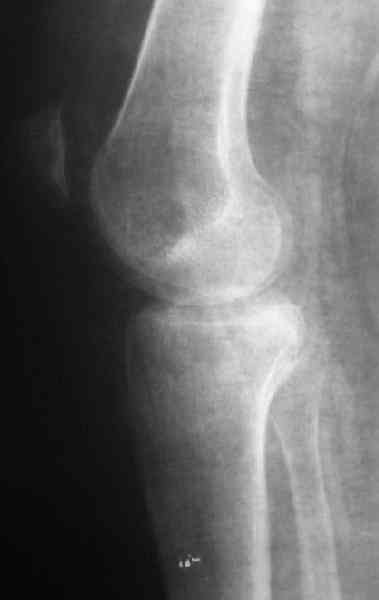

По тактике лечения, более импонирует второй вариант, но наружная плато расколота и туда при нагрузке внедряется н/мышелка бедра, поэтому после дистракции как репонирвать: или стяжными винтами, или изогнутами спицами или субхондральная костная пластика?

Уважаемый Абдурашид. Если нет противопоказаний , то из оперативных способов, я бы рекомендовал следующие: Полное замещение наружного мыщелка аллотрансплантатом либо открытая репозиция с элевацией и замещение дефекта ауто или аллокостью. В Ваших условиях , я бы рекомендовал второй способ. Во-время элевации необходимо разъединить фрагменты со стороны сустава ( надсечь скальпелем по линиям перелома, а затем тонким остеотомом их разъединить. При помощи долота произвести неполную остеотомию ( захватите не менее 1,5 - 2 см губчатой кости и поднять фрагменты, визуально отрепонировать и фиксировать 2-3 спицами. Дефект заместить костным ауто или аллатрансплантатом. Окончательная стабилизация пластиной ( лучше с угловой стабильностью, либо АВФ - позволит спокойно устранить угловую деформацию.

Недавно поступила больная через 1,5- 2 месяца.